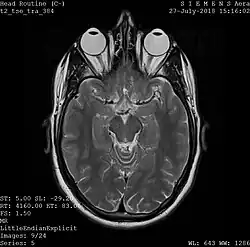

Magnetic resonance imaging

A magnetic resonance imaging instrument (MRI scanner), or "nuclear magnetic resonance (NMR) imaging" scanner as it was originally known, uses powerful magnets to polarize and excite hydrogen nuclei (i.e., single protons) of water molecules in human tissue, producing a detectable signal which is spatially encoded, resulting in images of the body.[12] The MRI machine emits a radio frequency (RF) pulse at the resonant frequency of the hydrogen atoms on water molecules. Radio frequency antennas ("RF coils") send the pulse to the area of the body to be examined. The RF pulse is absorbed by protons, causing their direction with respect to the primary magnetic field to change. When the RF pulse is turned off, the protons "relax" back to alignment with the primary magnet and emit radio-waves in the process. This radio-frequency emission from the hydrogen-atoms on water is what is detected and reconstructed into an image. The resonant frequency of a spinning magnetic dipole (of which protons are one example) is called the Larmor frequency and is determined by the strength of the main magnetic field and the chemical environment of the nuclei of interest. MRI uses three electromagnetic fields: a very strong (typically 1.5 to 3 teslas) static magnetic field to polarize the hydrogen nuclei, called the primary field; gradient fields that can be modified to vary in space and time (on the order of 1 kHz) for spatial encoding, often simply called gradients; and a spatially homogeneous radio-frequency (RF) field for manipulation of the hydrogen nuclei to produce measurable signals, collected through an RF antenna.

Like CT, MRI traditionally creates a two-dimensional image of a thin "slice" of the body and is therefore considered a tomographic imaging technique. Modern MRI instruments are capable of producing images in the form of 3D blocks, which may be considered a generalization of the single-slice, tomographic, concept. Unlike CT, MRI does not involve the use of ionizing radiation and is therefore not associated with the same health hazards. For example, because MRI has only been in use since the early 1980s, there are no known long-term effects of exposure to strong static fields (this is the subject of some debate; see 'Safety' in MRI) and therefore there is no limit to the number of scans to which an individual can be subjected, in contrast with X-ray and CT. However, there are well-identified health risks associated with tissue heating from exposure to the RF field and the presence of implanted devices in the body, such as pacemakers. These risks are strictly controlled as part of the design of the instrument and the scanning protocols used.

Because CT and MRI are sensitive to different tissue properties, the appearances of the images obtained with the two techniques differ markedly. In CT, X-rays must be blocked by some form of dense tissue to create an image, so the image quality when looking at soft tissues will be poor. In MRI, while any nucleus with a net nuclear spin can be used, the proton of the hydrogen atom remains the most widely used, especially in the clinical setting, because it is so ubiquitous and returns a large signal. This nucleus, present in water molecules, allows the excellent soft-tissue contrast achievable with MRI.[13]

A number of different pulse sequences can be used for specific MRI diagnostic imaging (multiparametric MRI or mpMRI). It is possible to differentiate tissue characteristics by combining two or more of the following imaging sequences, depending on the information being sought: T1-weighted (T1-MRI), T2-weighted (T2-MRI), diffusion weighted imaging (DWI-MRI), dynamic contrast enhancement (DCE-MRI), and spectroscopy (MRI-S). For example, imaging of prostate tumors is better accomplished using T2-MRI and DWI-MRI than T2-weighted imaging alone.[14] The number of applications of mpMRI for detecting disease in various organs continues to expand, including liver studies, breast tumors, pancreatic tumors, and assessing the effects of vascular disruption agents on cancer tumors.[15][16][17]